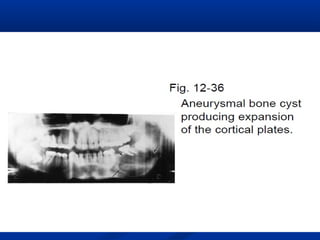

Aneurysmal bone cyst

 Aneurysmal bone cyst is not classified as

a true bony cyst because the lesion does

not have an epithelial lining.

 The lesion consists of fibrous connective

tissue stroma containing many cavernous

or sinusoidal blood-filled spaces. The

rapid growth of the lesion produces

expansion of the cortical plates but does

not destroy them.

 On a radiograph, the lesion appears as a well-circumscribed

unilocular or multilocular cystic lesion causing expansion of cortical

plates and resulting in a ballooning or "blow-out" appearance.

 The radiolucency is traversed by thin septa, giving it a soap bubble

appearance. The teeth are vital and may sometimes be displaced

with or without concomitant external root resorption